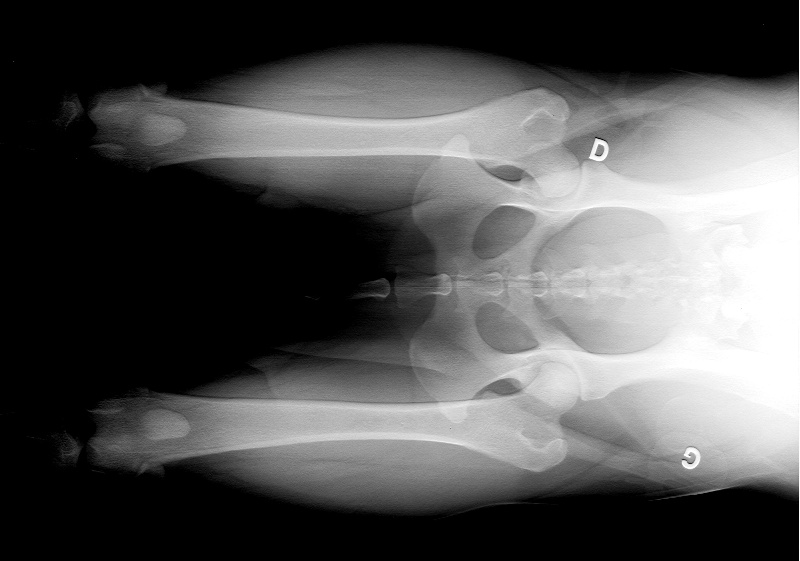

Test de comportement RACP : apte dysplasie : A |